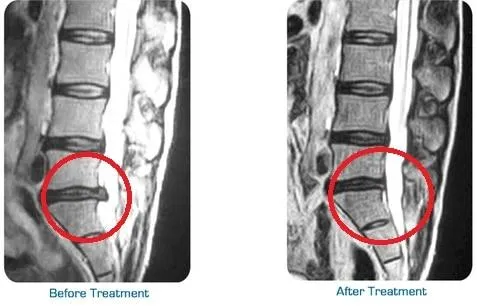

Helps reduce pain from herniated or bulging discs

Healthy spinal discs require consistent blood flow to deliver oxygen and nutrients necessary for repair and maintenance. Unfortunately, when discs are compressed, this circulation can be restricted, slowing the healing process. Spinal decompression therapy works to improve blood flow by gently stretching the spine and reducing tension around the discs.

As circulation improves, your body can more effectively deliver essential nutrients to the damaged areas, accelerating the healing process. This enhanced nutrient exchange helps reduce inflammation and promotes tissue regeneration, supporting your spine’s natural ability to repair itself. By restoring proper blood flow, spinal decompression ensures long-term improvements in your spinal health.